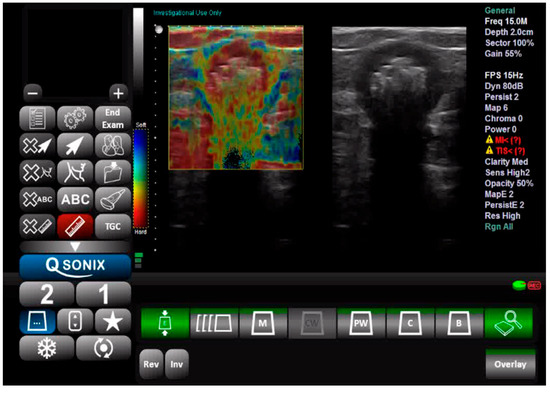

Tissue elasticity was reconstructed within the region of interest and translated into a color-coded signal superimposed on the grayscale image. To visualize tissue elasticity, different elasticity values corresponded to different colors (ranging from 1 to 256). The system was set to use a red/green/blue color map, where hard tissue areas were marked in red, intermediate tissues in green, and soft tissue areas in blue (Figure 1). The full spectrum from blue to red was applied to each elastographic determination. The degree of tissue compression was evaluated using a numerical scale from 1 to 5 in each image. Each recorded elastographic video was subjected to dynamic computer analysis using image processing software (ImageJ, version 1.53i, NIH, University of Wisconsin, Milwaukee, WI, USA). Histograms were generated for the three primary colors (red/green/blue) from a representative frame for each video, with each hue corresponding to an intensity value based on the number of pixels occupied by that hue in the selected frame (Figure 2). The numerical values thus obtained were subsequently analyzed statistically.

Figure 1. Ultrasound and elastography assessment of the sigmoid colon.